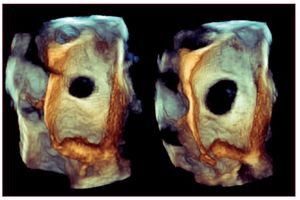

El intervencionismo valvular acapara un interés mediático en cardiología y supone una auténtica revolución en el tratamiento16. Esto implica unos niveles de formación específicos que se deben normalizar y ya hay publicaciones con los requisitos que deben cumplir los operadores de ecocardiografía en los laboratorios de hemodinámica17,18. En cuanto a la valoración anatómica del septo interauricular mediante RT-3DE en ETE para los cierres de defectos del tabique, hay un conocimiento profundo y fácilmente aplicable19. En la cuantificación del cortocircuito en el foramen oval permeable se demuestra que la sensibilidad del Doppler transcraneal y el ecograma transtorácico es similar, alrededor del 70%, superior a la del ETE, que tiende a subestimarlo20. Para la cuantificación de las comunicaciones interauriculares, el RT-3DE en ETE es la mejor técnica21, con la limitación del diámetro cambiante del defecto a lo largo del ciclo (fig. 2).

Figura 2. La comunicación interauricular varía de morfología y diámetro a lo largo del ciclo cardiaco, como puede verse en este plano obtenido con ecografía tridimensional en tiempo real transesofágica.